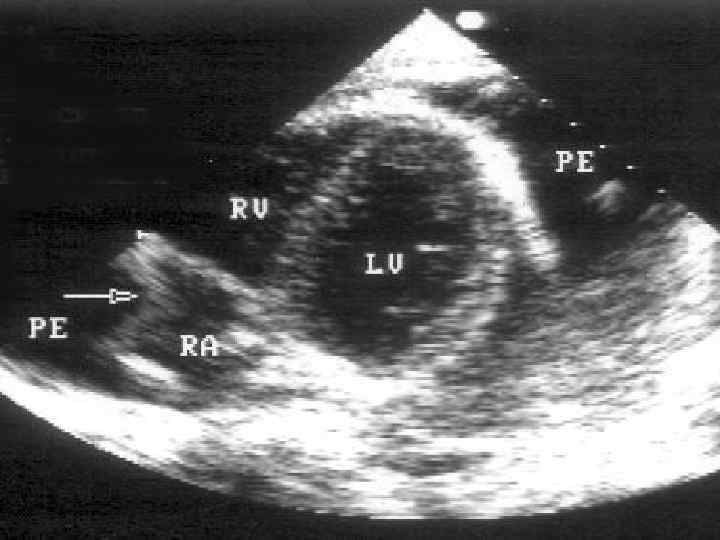

ЭХОКГ • Увеличение количества жидкости в перикарде • Расслоение листков перикарда от 3 мм до 2 -3 см • Яркое свечение листков перикарда • Утолщение листков перикарда • Появление диастолической дисфункции миокарда • Втяжение стенки правого желудочка при тампонаде сердца

ЭХОКС • При наличии небольшого выпота в перикарде обнаруживается относительно свободное от эхо-сигнала пространство между задней частью перикарда и задней частью эпикарда левого желудочка. • При большем объеме выпота это пространство располагается между передней частью перикарда правого желудочка и париетальной частью перикарда непосредственно под передней грудной стенкой.

При тампонаде правые отделы сердца очень чувствительно реагируют на фазы дыхания. • На вдохе кровенаполнение правых отделов увеличивается, что приводит к увеличению их диастолических размеров • На выдохе, наоборот, приток крови к правым отделам уменьшается, давление в них падает до уровня давления в перикарде и ниже • Это приводит к коллабированию правого предсердия и желудочка, что проявляется инвагинацией (прогибанием внутрь) их свободных стенок

• В то время как правые отделы на выдохе спадаются (коллабируют), левый желудочек увеличивается. Эти реципрокные изменения приводят к pulsus paradoxus. • Механизм увеличения размеров левого желудочка: напряженный выпот в полости перикарда оставляет ограниченное пространство для кровенаполнения сердца, в результате при уменьшении объема правого желудочка (на выдохе) левый желудочек увеличивается и, наоборот, при увеличении правого желудочка (на вдохе) левый желудочек уменьшается.

• Если при М-модальном исследовании правого желудочка субкостально на уровне чуть ниже атриовентрикулярного отверстия выявлено уменьшение его полости менее чем до 1 см, то это должно вызвать сильные подозрения на тампонаду сердца

• При начинающейся тампонаде сердца увеличение давления в полости перикарда препятствует наполнению правого желудочка и, следовательно, нормальному коллабированию нижней полой вены. • Это первый признак развивающейся тампонады сердца: недостаточное коллабирование нижней полой вены появляется еще до спадения правых отделов сердца на выдохе.

• Коллабирование нижней полой вены после глубокого вдоха составляет менее 50%. • Имеется сильная связь между давлением в правом предсердии и поведением нижней полой вены. • При коллабировании ее менее, чем на 50%, указывает на то, что давление в правом предсердии превышает 10 мм рт. ст. ,